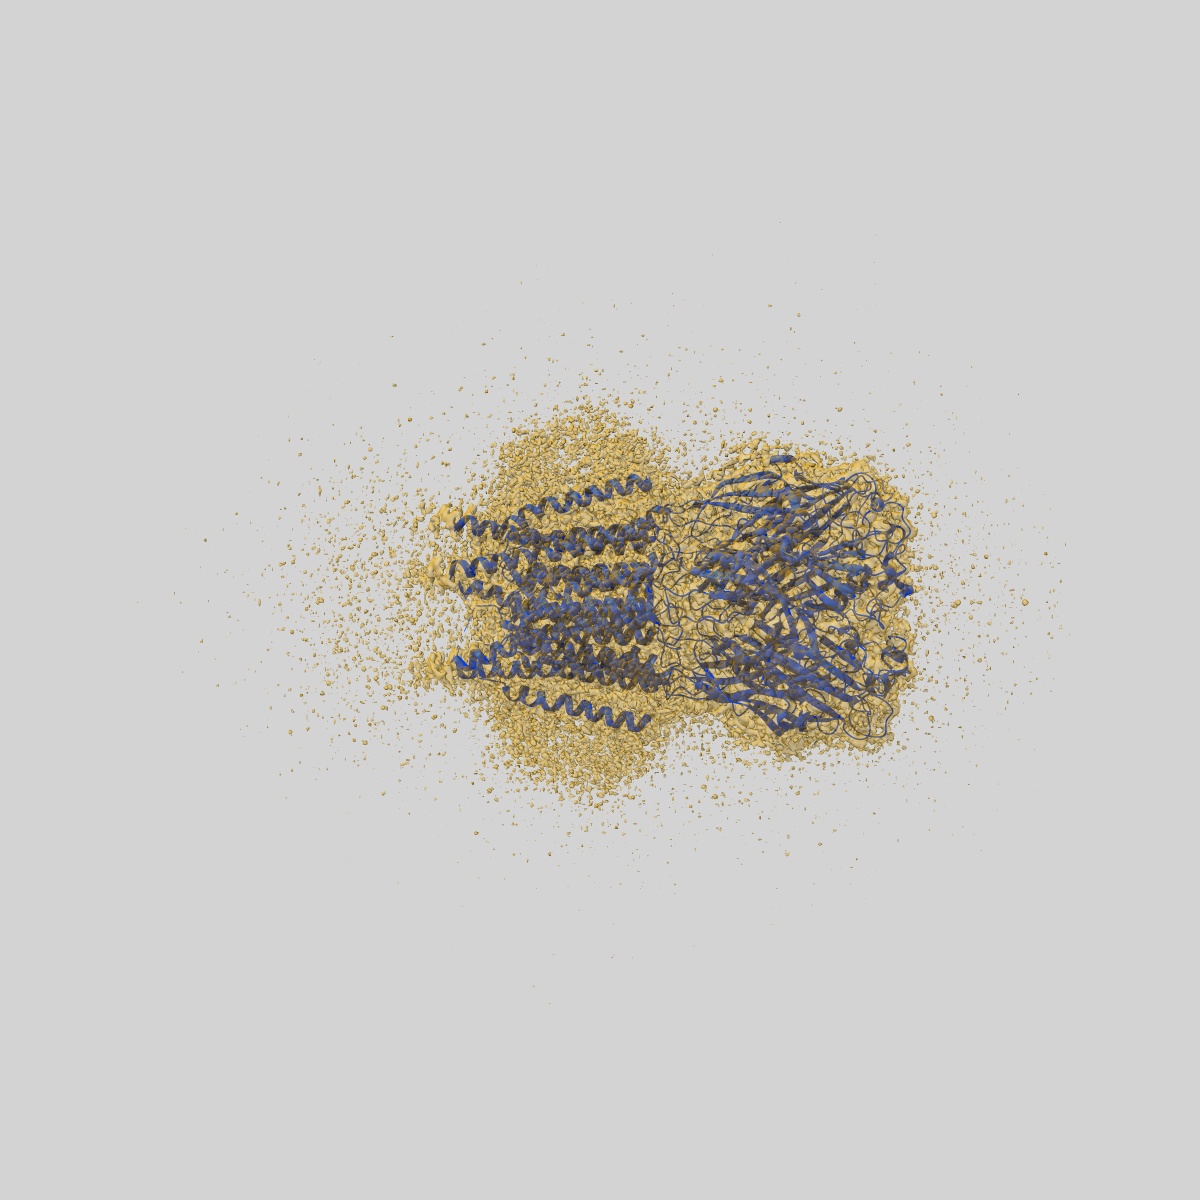

CryoEM structure of human rho1 GABAA receptor in complex with (R)-GABOB in the primed state

Sample: human rho1 GABAA receptor

Fitted models: 9frh

Cryo-EM structures of rho 1 GABA A receptors with antagonist and agonist drugs.

Fan C , Cowgill J , Howard RJ , Lindahl E

(2025) Nat Commun , 16 , 7077 - 7077